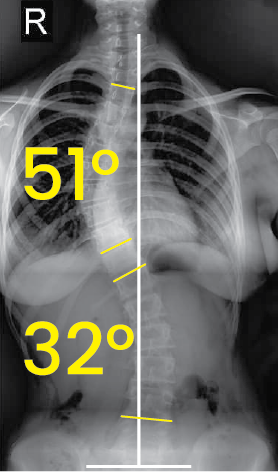

Belirgin 51° ve 32° dereceleri ile işaretlenmiş, omurgada eğriliği gösteren toraks ve karın bölgesi röntgeni.Göğüs ve bel bölgesinde 39° ve 15° eğim açılarını gösteren omurga röntgeni.